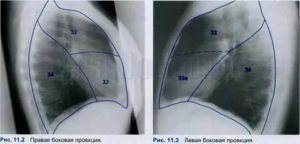

Сегментарное строение органа на обычном снимке анализировать сложно, поскольку сегментам свойственно наслоение одного на другой. Поэтому для правильной диагностики нужно проводить обследование в боковой проекции.

Рентген, проходя через легочную паренхимы, четко не выделяет топографические ориентиры, позволяющие локализовать сегментарную структуру легких. Чтобы на снимке научиться определять расположение патологических затемнений в легких, врачи-рентгенологи пользуются метками.

Слева сегментарное строение несущественно отличается, что позволяет врачу-рентгенологу на снимках в прямой и боковой проекциях достаточно точно локализовать патологические тени в легочной паренхиме.

Проведение снимка в прямой и боковой проекции позволяет точно установить локализацию и сегмент патологического процесса в легких.

Поскольку сегменты наслаиваются друг на друга, то их детальное изучение проводится на снимке в боковой проекции.

Правое легкое представлено десятью сегментами. В куполе располагается 1-й сегмент верхушки. От его задней поверхности начинается задний С2 верхней доли, а от передненаружной – С3.

С4 средней доли находится снаружи, располагается между горизонтальной щелью и нижними отделами косой. Впереди находится С5.

Если провести воображаемую линию от добавочной междолевой щели назад, то она станет нижней границей 6-го сегмента нижней доли. Сегменты с С7 по С10 расположены в ее основании. Наиболее медиальный – 7-й, он наслаивается на 8-й и 9-й, латеральный. Сзади расположен С10.

Слева их расположение несколько другое. С1-С3 объединены в большой задневерхушечный сегмент. Внизу, на месте средней доли расположен язычковый сегмент, который делится на С4 и С5.